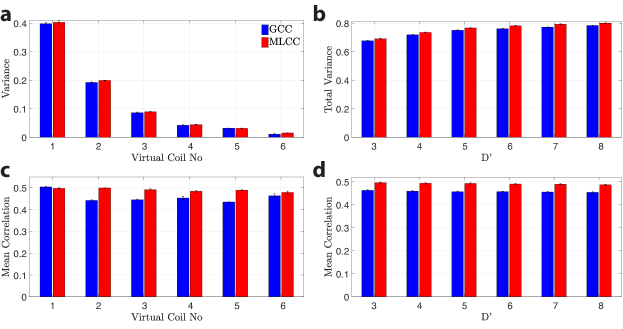

Next, the proposed coil compression –MLCC– was demonstrated on multi-coil data with D=32. Figure 6 displays the proportion of variance that is captured by =6 virtual coils, and the average correlation coefficient between pairs of virtual coil images for a representative subject. MLCC slightly improves variance explained in virtual coils compared to GCC. Furthermore, it increases the amount of shared information across acquisitions captured in coil-compressed data. This can be confirmed visually by virtual coils shown in Sup. Fig. S5. While coil sensitivities based on GCC vary substantially among acquisitions, MLCC yields more consistent coil sensitivities. Note that each acquisition in MLCC-based coils still shows intensity modulation due to bSSFP profiles. These results are valid in each individual subject. Because ReCat leverages an interpolation kernel to synthesize unacquired data across coils and acquisitions, consistency of virtual coils should enhance interpolation performance.

ReCat reconstructions and respective error maps following GCC and MLCC with =6 virtual coils are displayed in Fig. 7. For SPIRiT, PE-SSFP and ReCat, MLCC enables substantially reduced errors compared to GCC, as it increases the amount of information in virtual coils that is shared across multiple acquisitions. Quantitative assessments of coil-compressed ReCat reconstructions are listed in Table 3 for N=2-8, R=4-16, and =6. A comprehensive list of measurement for various reconstruction methods is in Sup. Table S5. For ZF, MLCC and GCC show no significant differences since they account for similar proportion of variance in coil data. For SPIRiT, PE-SSFP and ReCat, MLCC yields higher PSNR than GCC for all N and R (p0.05, sign-rank test). On average, MLCC improves PSNR by 0.80.6 dB over GCC for ReCat (meanstd across subjects; average for N=2-8, R=4-16).

Differences in PSNR of ReCat images obtained after MLCC and GCC are plotted in Sup. Fig. S6 for varying =[3, 8] in a representative subject. For 4, MLCC consistently improves PSNR over GCC regardless of R or N. Taken together, these results suggest that the proposed framework enables scan-efficient phase-cycled bSSFP imaging at high R with improved image quality due to the tensor-based reconstruction and coil compression.